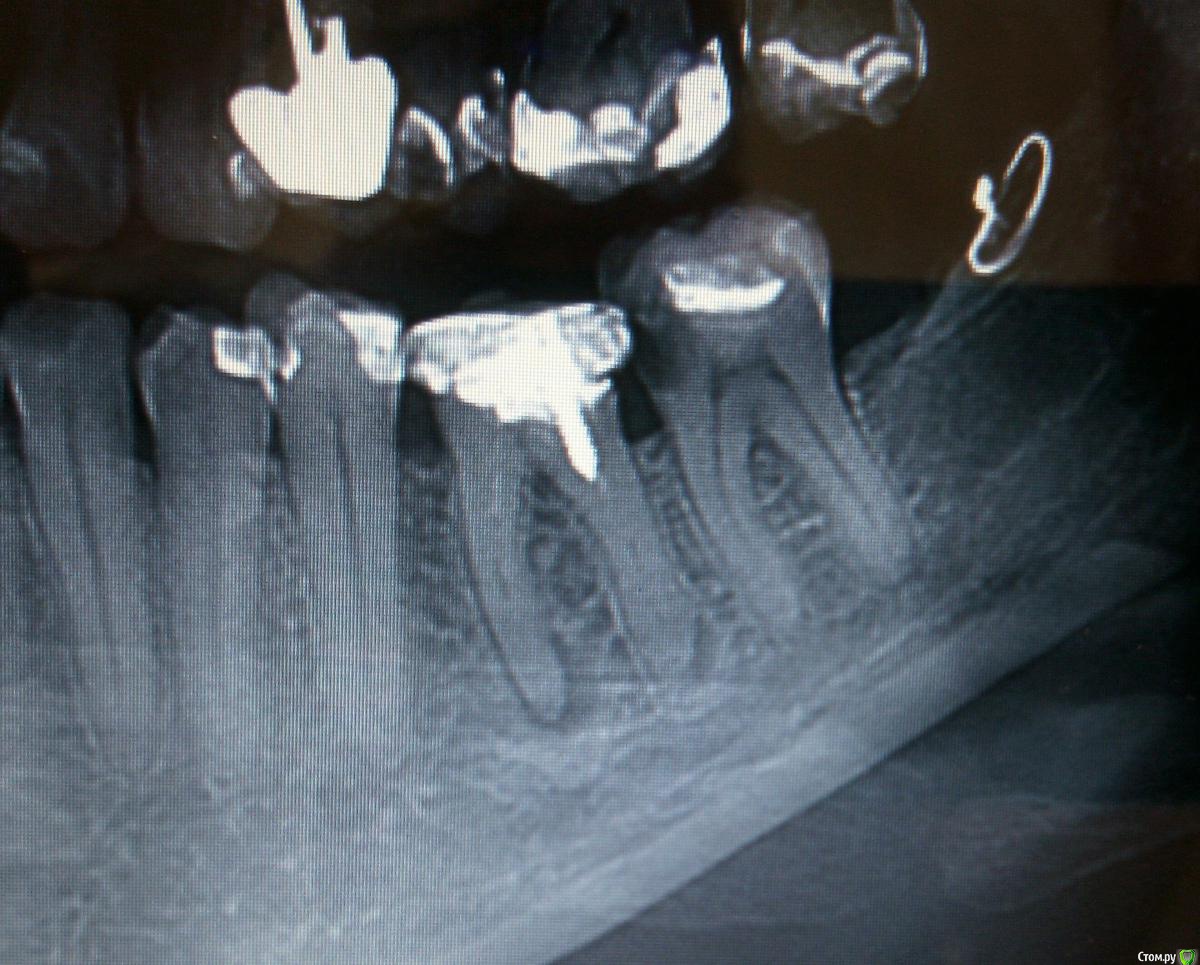

igorstom Опубликовано 24 ноября, 2019 Автор Поделиться Опубликовано 24 ноября, 2019 Вот полюбуйтесь на эти "шедевры". Это дети 10,14,15 лет. Коронки показаны? Да без сомнения. Да такое каждый день вижу. И в дорогих клиниках большинство работ оставляет желать лучшего. Ссылка на комментарий